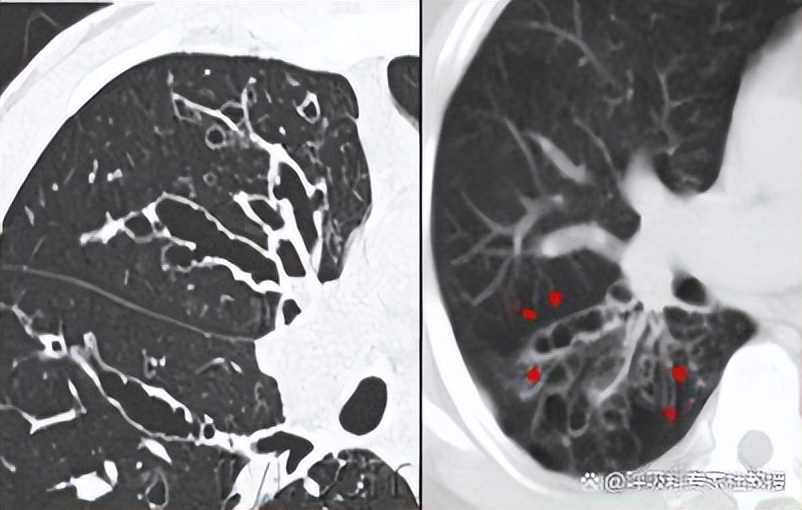

一、轨道征:由增厚的支气管壁和扩张中空的支气管共同构成,边缘平滑,和火车轨道十分相似,当CT切面与支气管平行时,即可表现出轨道征,是柱状支扩的典型影像特征。

二、印戒征:听到这个名字,可能很多人会想到印戒细胞癌,这是一种恶性程度比较高的肿瘤,而支扩也有这么一个典型征象,从名字可以看出,其形象类似戒指,当CT切面与支气管垂直时,可表现为印戒征,因支扩后内径超过伴行肺动脉而形成。